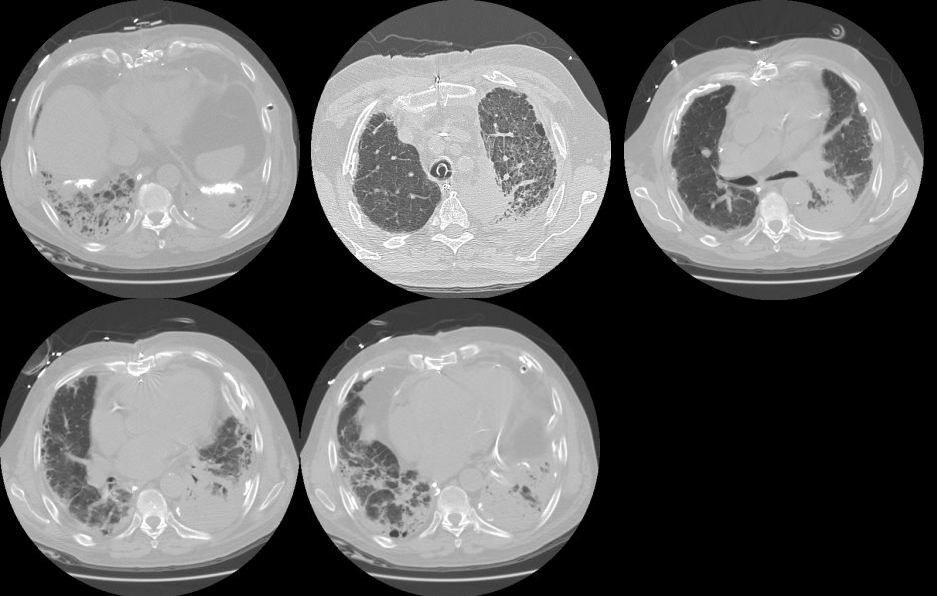

Age: 83

Sex: Male

Indication: Pre-op

Sample ReportBilateral pleural plaques and interstitial coarsening, most prominent at the lung bases. Findings are most suggestive of asbestosis. Consider chest CT for further evaluation.

No definite superimposed focal airspace disease.

Mild cardiomegaly.